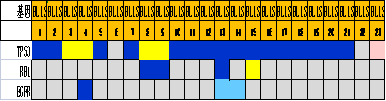

通过进一步基因表达谱测序���,对组织形态学和免疫组化水平界定的TNBC亚型的基因变异情况进行分析����,筛选各亚组之间的差异表达基因及表达意义探究��,结果显示���:1.免疫治疗相关的生物标记物MSI-H��、TMB-H����,作为一个低频发生事件����,在TNBC中不太可能常规作为免疫治疗有效性的评估手段��;TNBC的MSI发生机制可能与结直肠癌不同����、突变热点不同��。2. 整个研究队列中基因表达存在明显差异��,充分显示了患者个体间差异的存在����,从分子水平揭示了TNBC是一种高度异质性肿瘤��。3. TP53基因变异率发生最高��,提示在TNBC形成中可能扮演非常重要的角色����。4. TNBC分型的基因表达聚类分析方面存在差异(图2)����,这些差异基因参与了多种不同的生物学通路��,筛选特异的分子标记物或靶向治疗的靶点以期指导临床治疗���。

图2. 基于组织形态学及免疫组织化学标记物的TNBC亚型的基因表达聚类分析